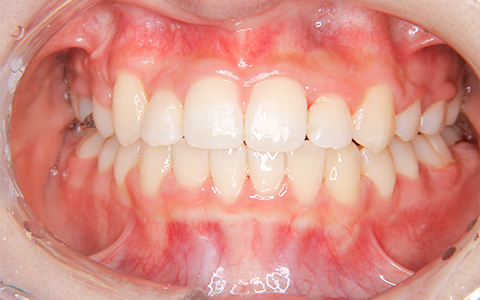

治療前

治療後

施術内容 開咬、上顎前突に対するマルチブラケット装置による抜歯(上下顎両側第一小臼歯を抜歯)治療(18歳)

治療期間 2年3ヵ月(通院27回)

費用 880,000円

リスク・副作用 歯が動く痛み、歯髄壊死、歯根吸収、歯肉退縮、リテーナーを使用しないことによる後戻り